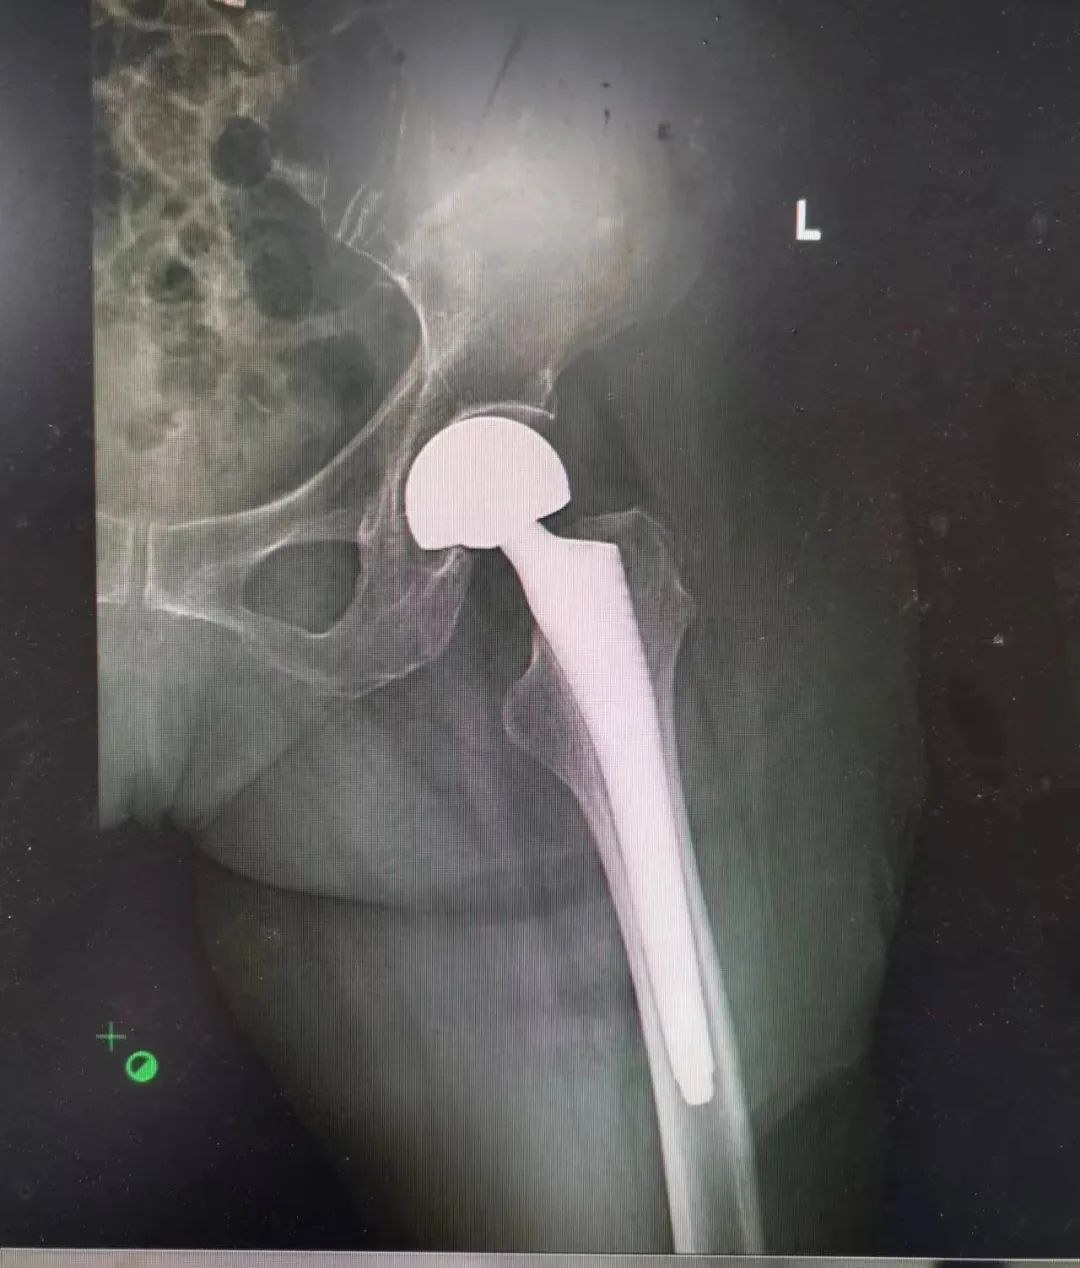

手术当天非常顺利,陕西冶金医院骨科赵学刚主任主刀,为患者实施人工半髋关节置换术。

▲ 图:术后X光片